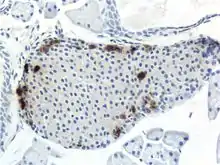

The pancreas serves multiple roles within mammalian organisms. It plays a role in the digestive system and the endocrine system making it an organ and a very important gland.[2] PP cells tend to located in the pancreatic islets, and are one of the rarer pancreatic cell types.[1] Some small clusters may also be found surrounded by exocrine pancreas.[3] They tend to be located in the duodenal part of the pancreas more medially.[3] Given their location in pancreatic islets along with their low population, they are able to respond efficiently to changes in blood sugar, nerve impulses, and chemical signaling through gap junctions or cellular signaling. PP cells show the highest concentration at the head of the pancreas.[1]

Through different microscopy techniques, the structural related details of PP cells have been able to be better understood. This is inclusive of how big they are, what their cellular membranes look like, the proteins associated with them, and even their size. PP cells are elongated cells. Another one of these details can be noted in insulins secretory granules, or container like buds, that store insulin within a cell. In PP cells, the size of the insulin granules are smaller and spherical and similar to those in alpha cells. This is noted in human PP cells, but different animals have been shown to have different sized granules compared to humans, like rodents. In cats and dogs, PP cells have large granules.[8] In rats, PP cells have few granules, similar to humans. In dogs, some PP cells are located in the walls of the antrum of the stomach.[3]